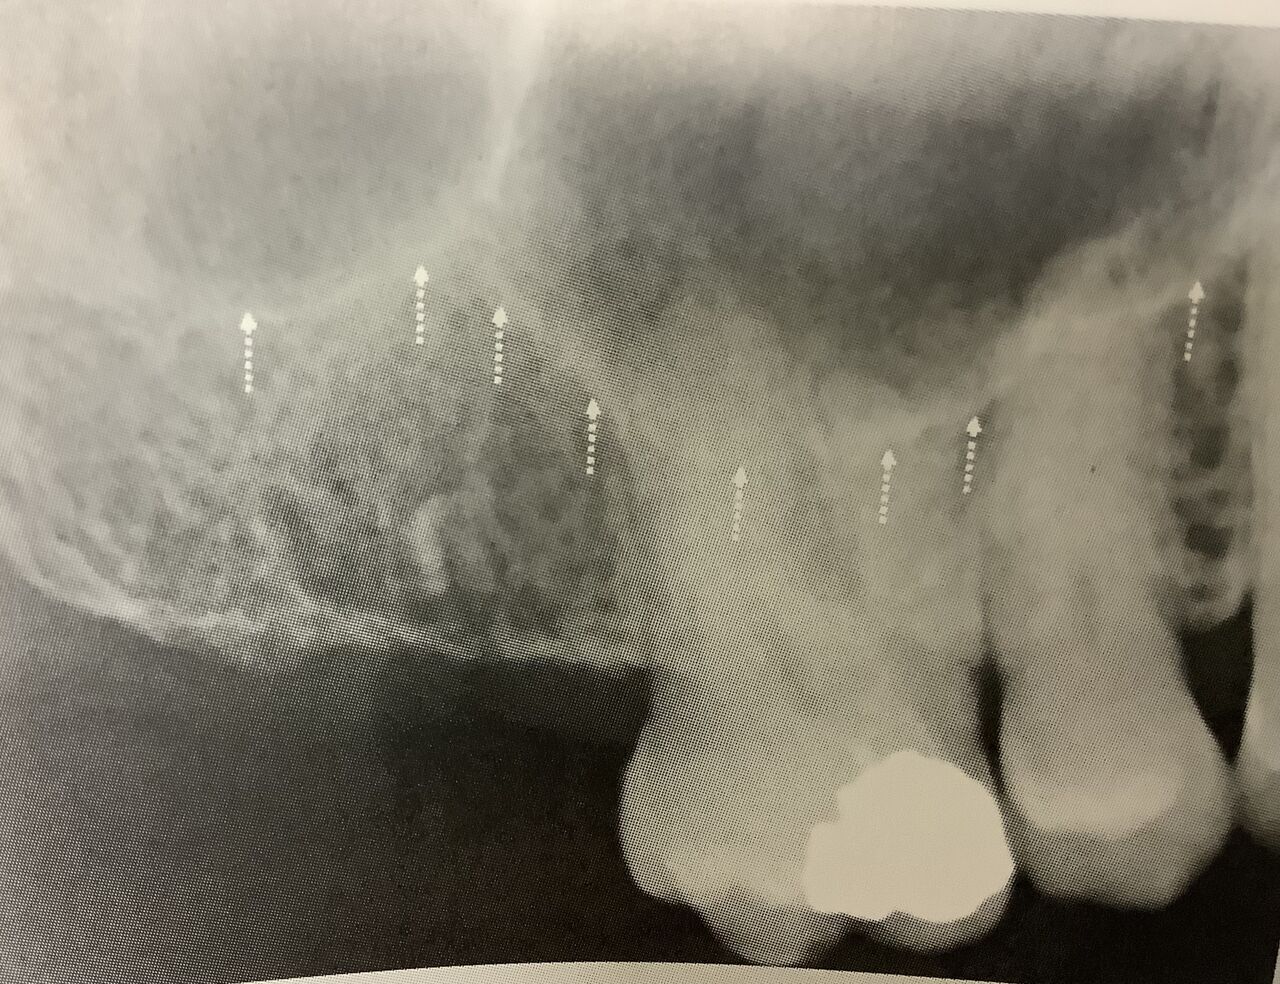

上の奥歯の上にあって、空気が入っているので黒っぽく見えます。

レントゲンで白くハッキリとした境目、フチに囲まれて見えます。

で、その中にハリがあって分かれています。

大きさも様々で、歯の根っこの間や下の方まで広がっている時もあります。

奥歯を抜くと、この空洞が大きくなって下まで広がることが多いんです。

歯と近いので、お互いに影響し合う重要な場所です。